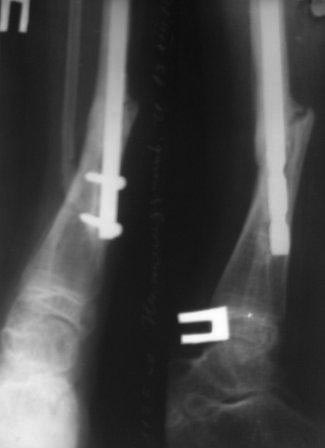

Уважаемые коллеги! помогите советом! Мальчик 2000 г.р. В 2007г получил

перелом н/з костей правой голени,

в районе лечили гипсом 6 месяцев, сращения нет, в обл.центре КДО

аппаратом Илизарова - 3 месяца, после повторная деформация, в НИИТО КДО

аппаратом Илизарова -7 месяцев, перелом якобы сросся, но после снятия

аппарата через 2 недели после незначительной травмы повторный перелом. И

было произведена после рассверливания канала БИОС плечевым стержнем,но

стержень пошел по мед.стенке дистального отломка поэтому остался

некоторый вальгус(операция без ЭОП) ребенок через неделю начал

самостоятельно ходить, клинически деформации нет, все обрадовались,

выписали, повторно приехали только ч-з 1,5 года вот с такой деформацией,

но ребенок ходит в школу, бегает, незначительно хромает, родители

требуют исправить деформацию.